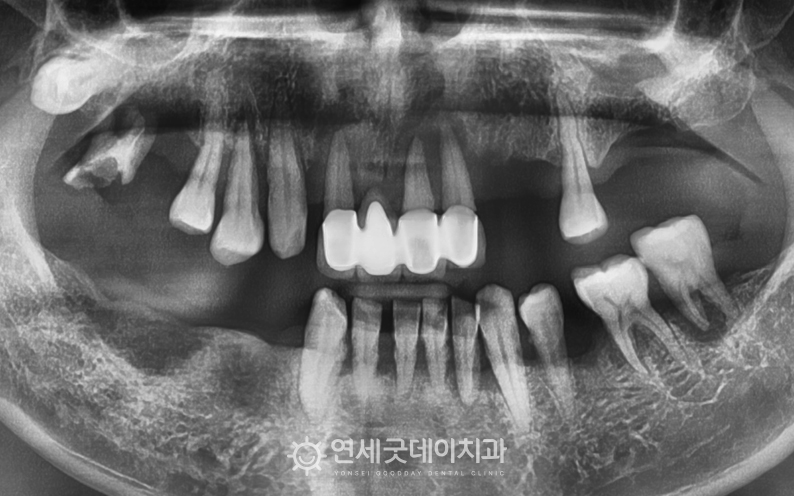

환자분은 중등도 이상의 치주질환으로 인해 이로 인해 치아 배열이 불규칙해지고

엑스레이 상에서도 상하악 모두 이 밖에도 좌우 어금니가 상실되었고

앞니 일부는 크라운으로 수복된 상태였으며 또한 잔존치의 예후도 좋지 않았기 때문에